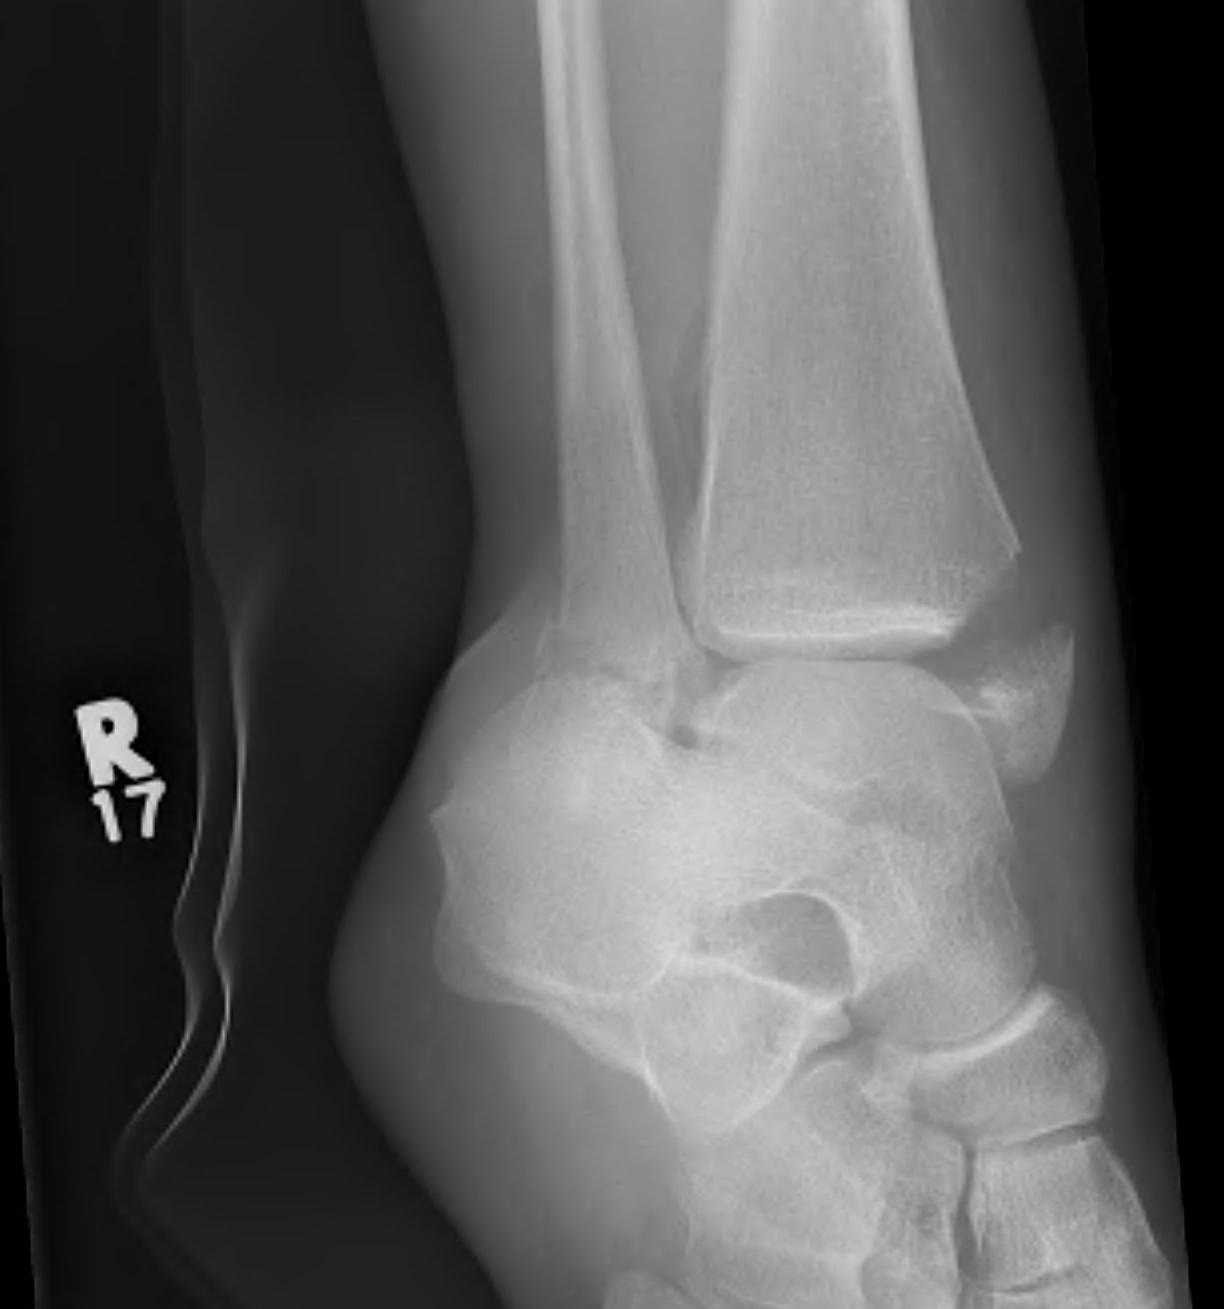

Ankle dislocation

Reduction under conscious sedation

- protects skin medially

- conscious sedation in emergency department

- well moulded cast

- unstable ankles need monitoring for loss of reduction

- can need external fixation to maintain position

Dislocationdislocationdislocation